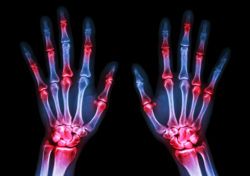

Gout is an arthritic condition in which uric acid builds up in a patient’s joints. Uric acid is naturally produced by cells and processed out of the body via the kidneys. In gout patients, the kidneys to not effectively filter out uric acid.

This can lead to a build-up of uric acid in the joints where it can form sharp, needle-like crystals resulting in tissue irritation and inflammation. Commonly reported gout symptoms include intense joint pain, lingering discomfort, inflammation, redness and limited range of motion.